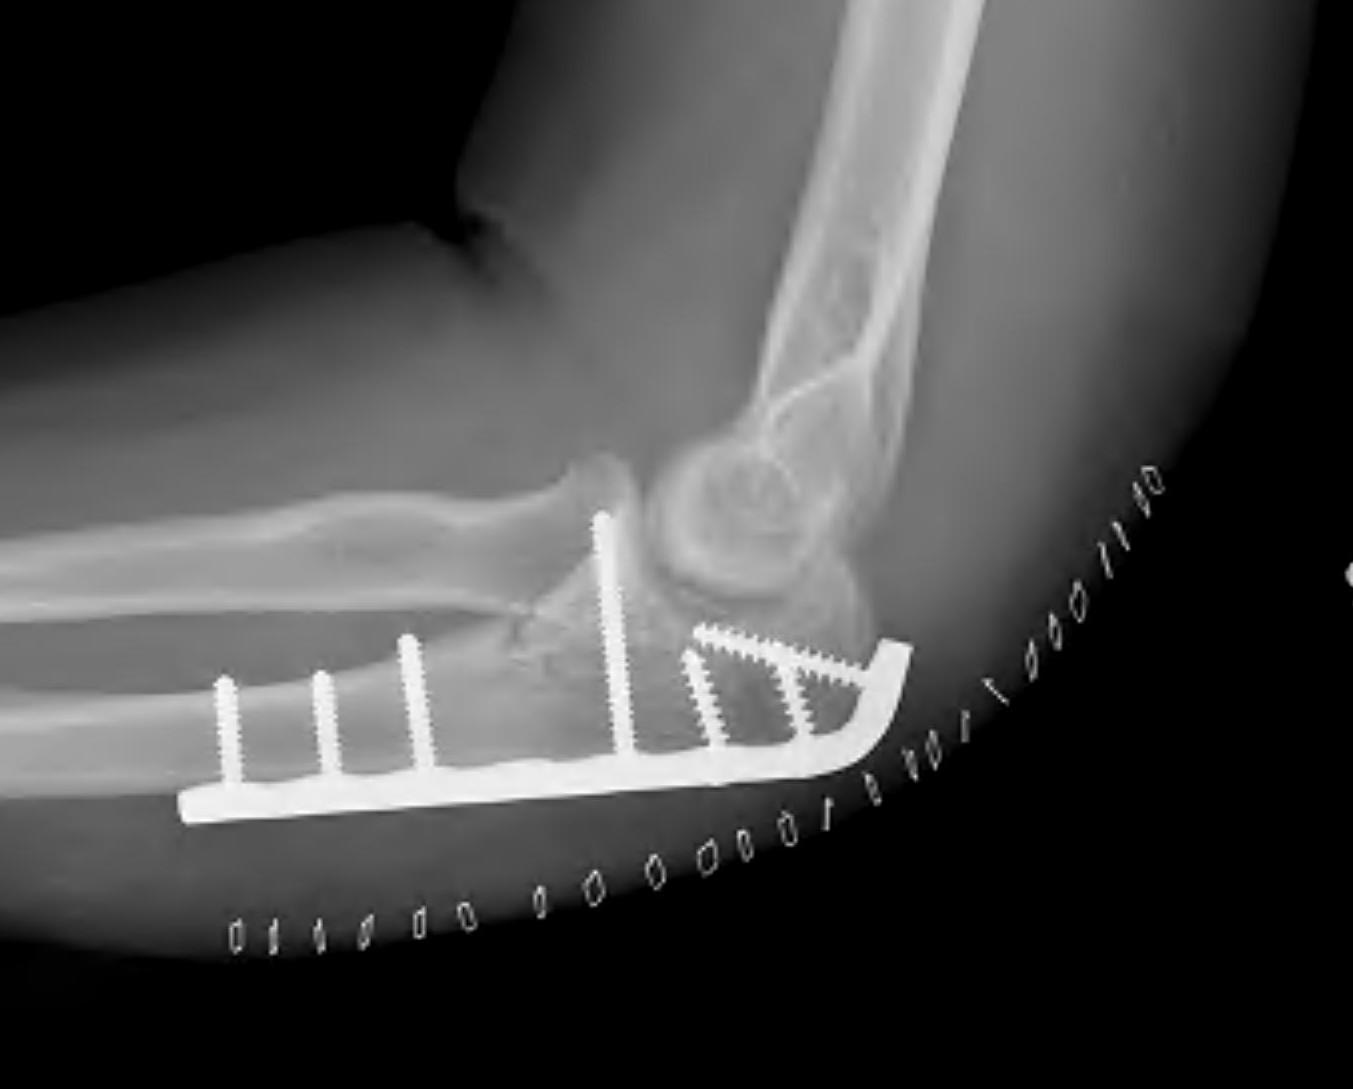

Olecranon plate + ORIF Type II coronoid process + radial head replacement

Olecranon plate with radial head replacement

Olecranon plate with radial head replacement + LCL repair

Olecranon plate + medial coronoid buttress plate + radial head replacement

Universal posterior approach

Identify olecranon fracture

- isolate and protect ulna nerve

- dissection out medial and lateral proximal ulna

- reduce and plate olecranon